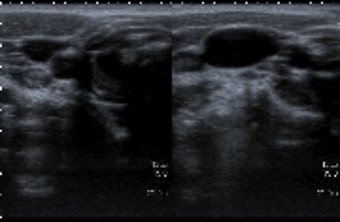

En la ecografía no presenta alteraciones significativas de forma basal. Al pedirle de nuevo que sople contra una resistencia, en la zona descrita presenta una imagen hipoecogénica homogénea, Doppler negativa, que aumenta de tamaño con el esfuerzo y desaparece por completo cuando este cede (Fig. 1). Se visualiza una glándula tiroidea de características normales.

Figura 1. Ecografía antes y después de hacer soplar al paciente.

La ecografía es la prueba de imagen de elección para emitir un diagnóstico más preciso en el estudio de las masas cervicales. La accesibilidad de dicha técnica en nuestro centro nos permitió descartar que se tratase de un proceso vascular, por ser Doppler negativo, y orientarlo a malformaciones cervicales con comunicación a la vía aérea (laringocele o quiste branquial).